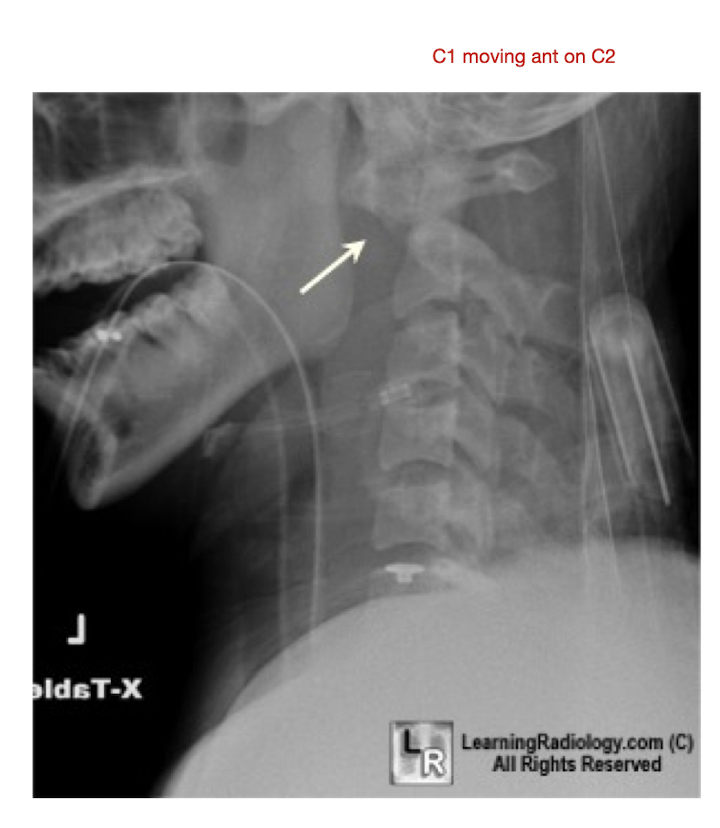

C/S: RA

What is it?

What does RA cause?

What 3 structures does it affect?

What is it?

Erosion and narrowing of the facet jts

Cause:

Increased Lig Laxity

Atlantoaxial Jt

Laxity of the Transverse Lig

Anterior Subluxation of C1 on C2